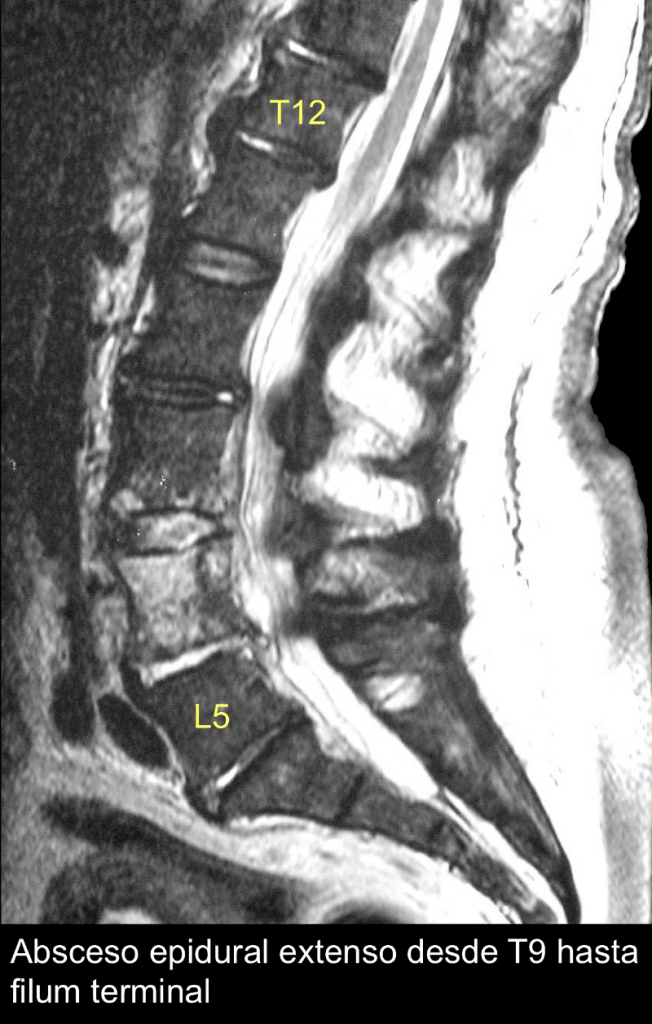

En total, 42 complicaciones infecciosas. El absceso epidural ocurrió en 13 pacientes, ocho mujeres (17-82 años; mediana 62 años) y cinco hombres (44-76 años; mediana 51 años). En 12 casos con absceso epidural postbloqueo epidural, se informó que tres pacientes estaban sanos previamente; de los restantes, 4 pacientes eran diabéticos, 3 pacientes tenían cáncer, un paciente con abuso crónico de alcohol y un paciente con artritis reumática bajo tratamiento crónico con esteroides sistémicos. Seis pacientes recibieron bloqueo epidural para aliviar el dolor por traumatismo; de estos, 5 recibieron bloqueo epidural torácico para aliviar el dolor por traumatismo torácico. El intervalo de tiempo entre la inserción del catéter y los primeros síntomas varió de 2 días a 5 semanas (mediana 5 días). En 2 casos, el catéter epidural se retiró antes de que aparecieran los primeros síntomas. El síntoma predominante fue fiebre y, a menudo, dorsolumbalgia intensa, en 5 casos con progresión a síntomas neurológicos. La RMN se utilizó para diagnosticar 10 casos; en un paciente fue con TAC previamente normal.

Los siete cultivos positivos mostraron especies de estafilococos. Se realizó laminectomía en 6 pacientes, con restablecimiento total en tres. En total, 7 pacientes tuvieron curación completa, mientras que 4 de los 5 pacientes que desarrollaron síntomas neurológicos no se recuperaron. Las secuelas que se informaron por síndrome de cauda equina en 2 pacientes, fueron paraparesia en uno y tetraplejia en otro. El último paciente, afectado por una enfermedad vascular, falleció. [Ver artículo completo]